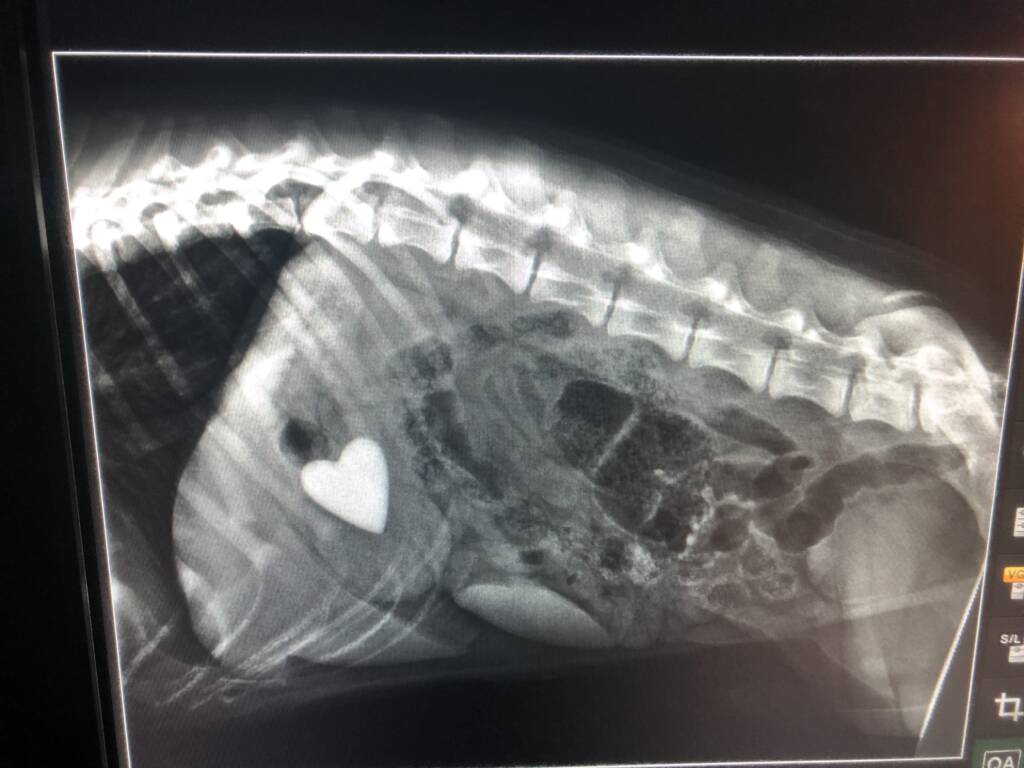

2021 They Ate What?! X-ray Contest winnersThey Ate This: Check out the winner, runners-up, and honorable mentions October 4, 2021 < Previous Entry VOTE NOW! Pages: 1 2 3 4 5 6 7 8 9 10 11 12 13 14